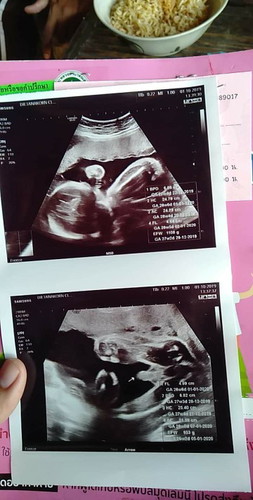

6เดือนกว่าได้ลูกแฝดค่ะ ไปซาวมา คน1 1108กรัม อีกคน953กรัมจ้า คุณแม่ช็อคไปเลยจ้า